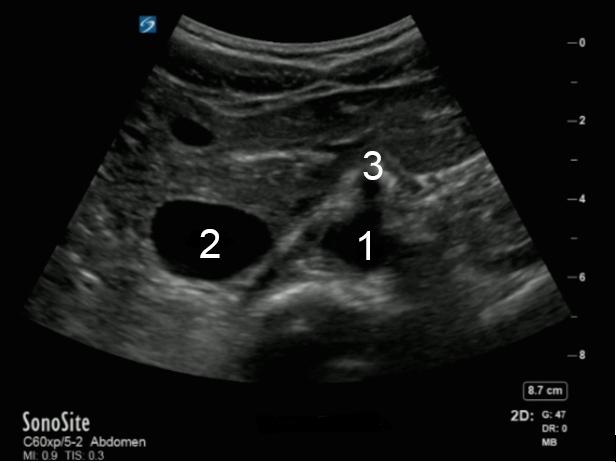

Aorta Celiac Trunk Transverse Image

Aorta

Inferior Vena Cava (IVC)

Celiac Artery (CA)